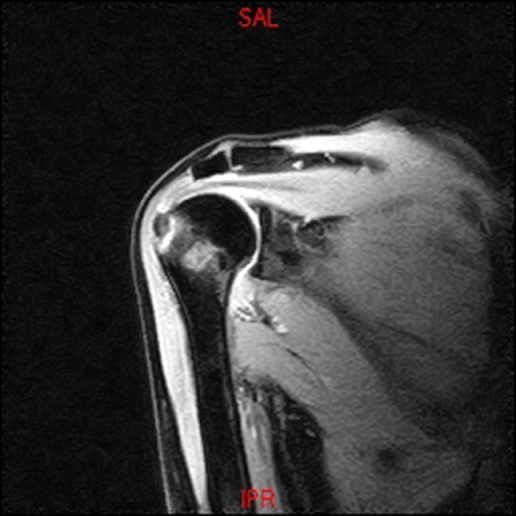

• RESONANCIA PATOLÓGICA DE HOMBRO - FRACTURA TROQUITER Y EDEMA OSEO -  COR T2 WF

• RESONANCIA NORMAL HOMBRO COR T1